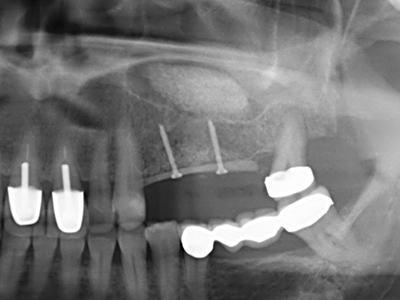

En la extracción de bloques óseos la piezocirugía también presenta ventajas adicionales: Además de la alta precisión en la osteotomía que ya se ha descrito antes, se ha comprobado que el uso de los delgados insertos de sierra resulta especialmente cuidadosas con el hueso. Frente a esto, sobre todo cuando se usan las fresas de Lindemann, cabe esperar pérdidas en la extracción significativamente más altas debido al mayor grosor de la parte frontal del cabezal (Lakshmiganthan, Gokulanathan et al. 2012). La separación basal que se necesita en particular en los injertos de bloque extraídos de forma retromolar se ve facilitada mediante sierras perpendiculares especialmente previstas a tal fin, lo que permite considerar que la cirugía piezoeléctrica es un procedimiento preciso y seguro para la obtención de bloques de hueso en el área retromolar (Happe 2007) (fig. 1-12).

Como ya se ha demostrado en el pasado, básicamente cualquier procedimiento de cirugía de hueso representa una posible indicación para la cirugía piezoeléctrica. Así, la preparación del segmento móvil en la osteogénesis de distracción (fig. 23-25) y en la osteotomía de sándwich puede realizarse con piezas especiales, sin poner en peligro el suministro sanguíneo de la parte crestal, que resulta esencial para el éxito de ambas técnicas (González-García, Diniz-Freitas et al. 2008).

En la cirugía del seno maxilar surgen otros campos de aplicación: En este punto, tras la preparación concéntrica de una tapa ósea de la pared del seno maxilar (que suele tener forma trapezoidal), es posible eliminar patologías y cuerpos extraños del seno maxilar. La tapa ósea se repone después de finalizar la parte intra-antral de la operación y se asegura frente a una posible dislocación mediante cuñas o suturas adaptables.